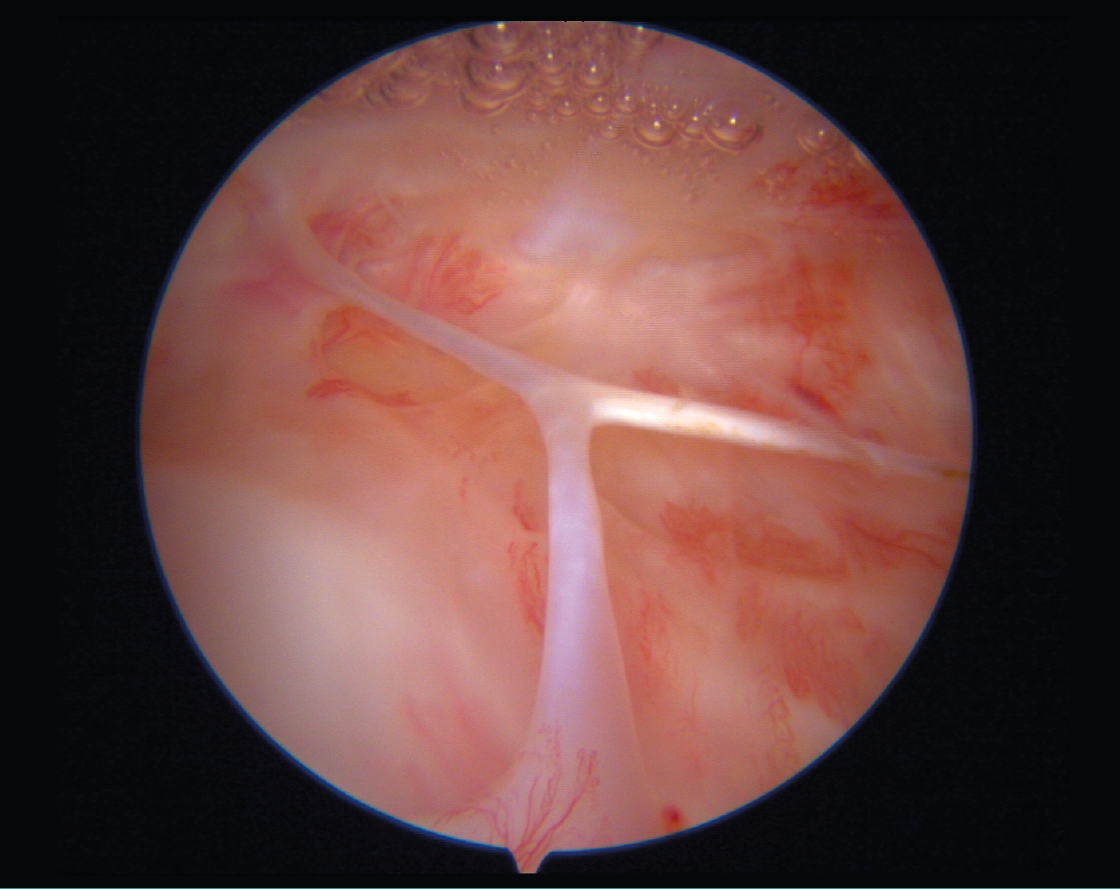

Curiosa imagen de tejido fibroso formando el símbolo de la paz hallado en el fondo del saco cuadricipital en una artroscopia de rodilla de revisión tras intervención del ligamento cruzado anterior (LCA) con síndrome del cíclope anterior posligamentoplastia del LCA.